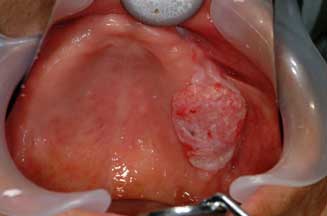

○ 非歯原性悪性腫瘍:症状として腫脹、違和感、接触痛を認めます。最も多いのは口腔粘膜上皮

より発生する扁平上皮癌、ついで小唾液腺、大唾液腺から発生する腺癌系です。その他、肉腫、

悪性リンパ腫などが発生します。扁平上皮癌の症状としては表面の潰瘍形成、腫瘤形成、白板形成

などです。腺癌は皮下または粘膜下組織の膨隆として触れることが多いです。

| 下顎歯肉癌(扁平上皮癌) | 上顎歯肉癌(扁平上皮癌) | |